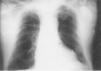

Ante lapersistencia del bloqueo AV completo, y tras descartar laintervención de medicación cardiodepresora y lapresencia de isquemia miocárdica aguda, se indicó unmarcapasos definitivo, que se implantó a las 24 h delingreso en UCI. Reingresó procedente de quirófanopara control inmediato del marcapasos definitivo portandoaún el electrocatéter transitorio. En unaradiografía de tórax anteroposterior de control, enla cama de UCI, se observó la correcta posición delelectrocatéter definitivo y la ubicaciónanómala del catéter transitorio, que perforaba elmiocardio (fig. 1). Inmediatamente se procedió a su retiradacontrolada por registro continuo de ECG intracavitorio proximal ydistal (fig. 2). No presentó ningún tipo decomplicación a pesar del hallazgo ecográfico dederrame pericárdico de 150-200 ml, que no comprometíala diástole de las cavidades derechas. Tras una semana deobservación fue dado de alta a su domicilio sinincidencias.

Fig. 1.Radiografía del paciente del caso clínico en que semuestra el electrocatéter que se introduce por subclaviaderecha y perfora el ventrículo derecho saliendo fuera delmediastino.